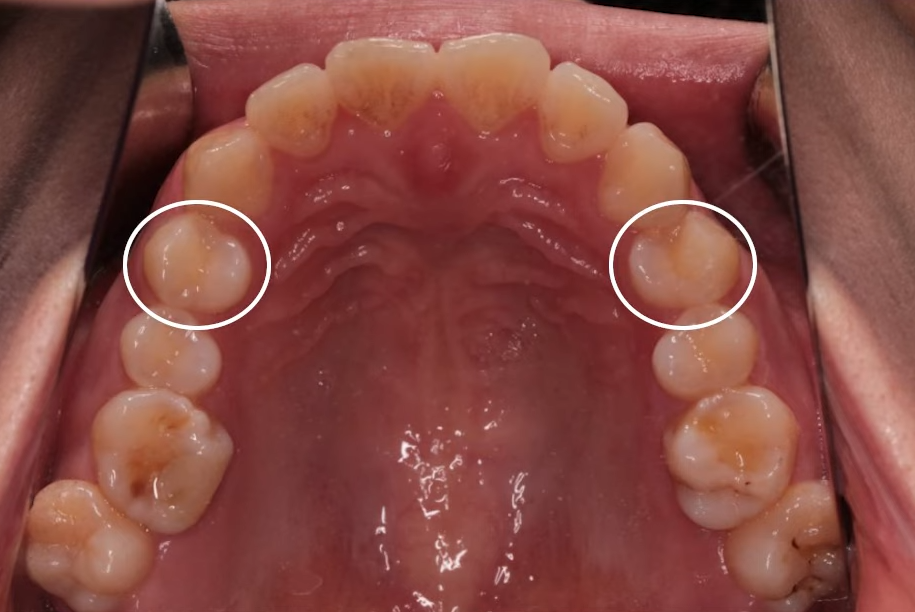

발치 + 인비절라인 돌출입 개선 사례

바로 사례부터 보여드릴게요.

"입이 나와 보여요"라며 찾아주신 여성 환자분이셨는데요.

치료 전 X-ray 측면 모습으로도 치아가 앞으로 기울어져 있고,

입이 튀어나온 모습을 확인할 수 있습니다.

돌출입수술은 무섭고, 회복도 걱정돼

비수술적인 방법을 찾다가 인비절라인을 선택하게 되셨는데요.

상악, 하악 각각 첫 번째 소구치를 발치했고,

인비절라인을 통해 치아를 뒤로 이동시키며 돌출을 점진적으로 개선했습니다.

뻐드러져 있던 치아 배열 모습이 정상적으로 돌아온 걸 확인하실 수 있을 겁니다.